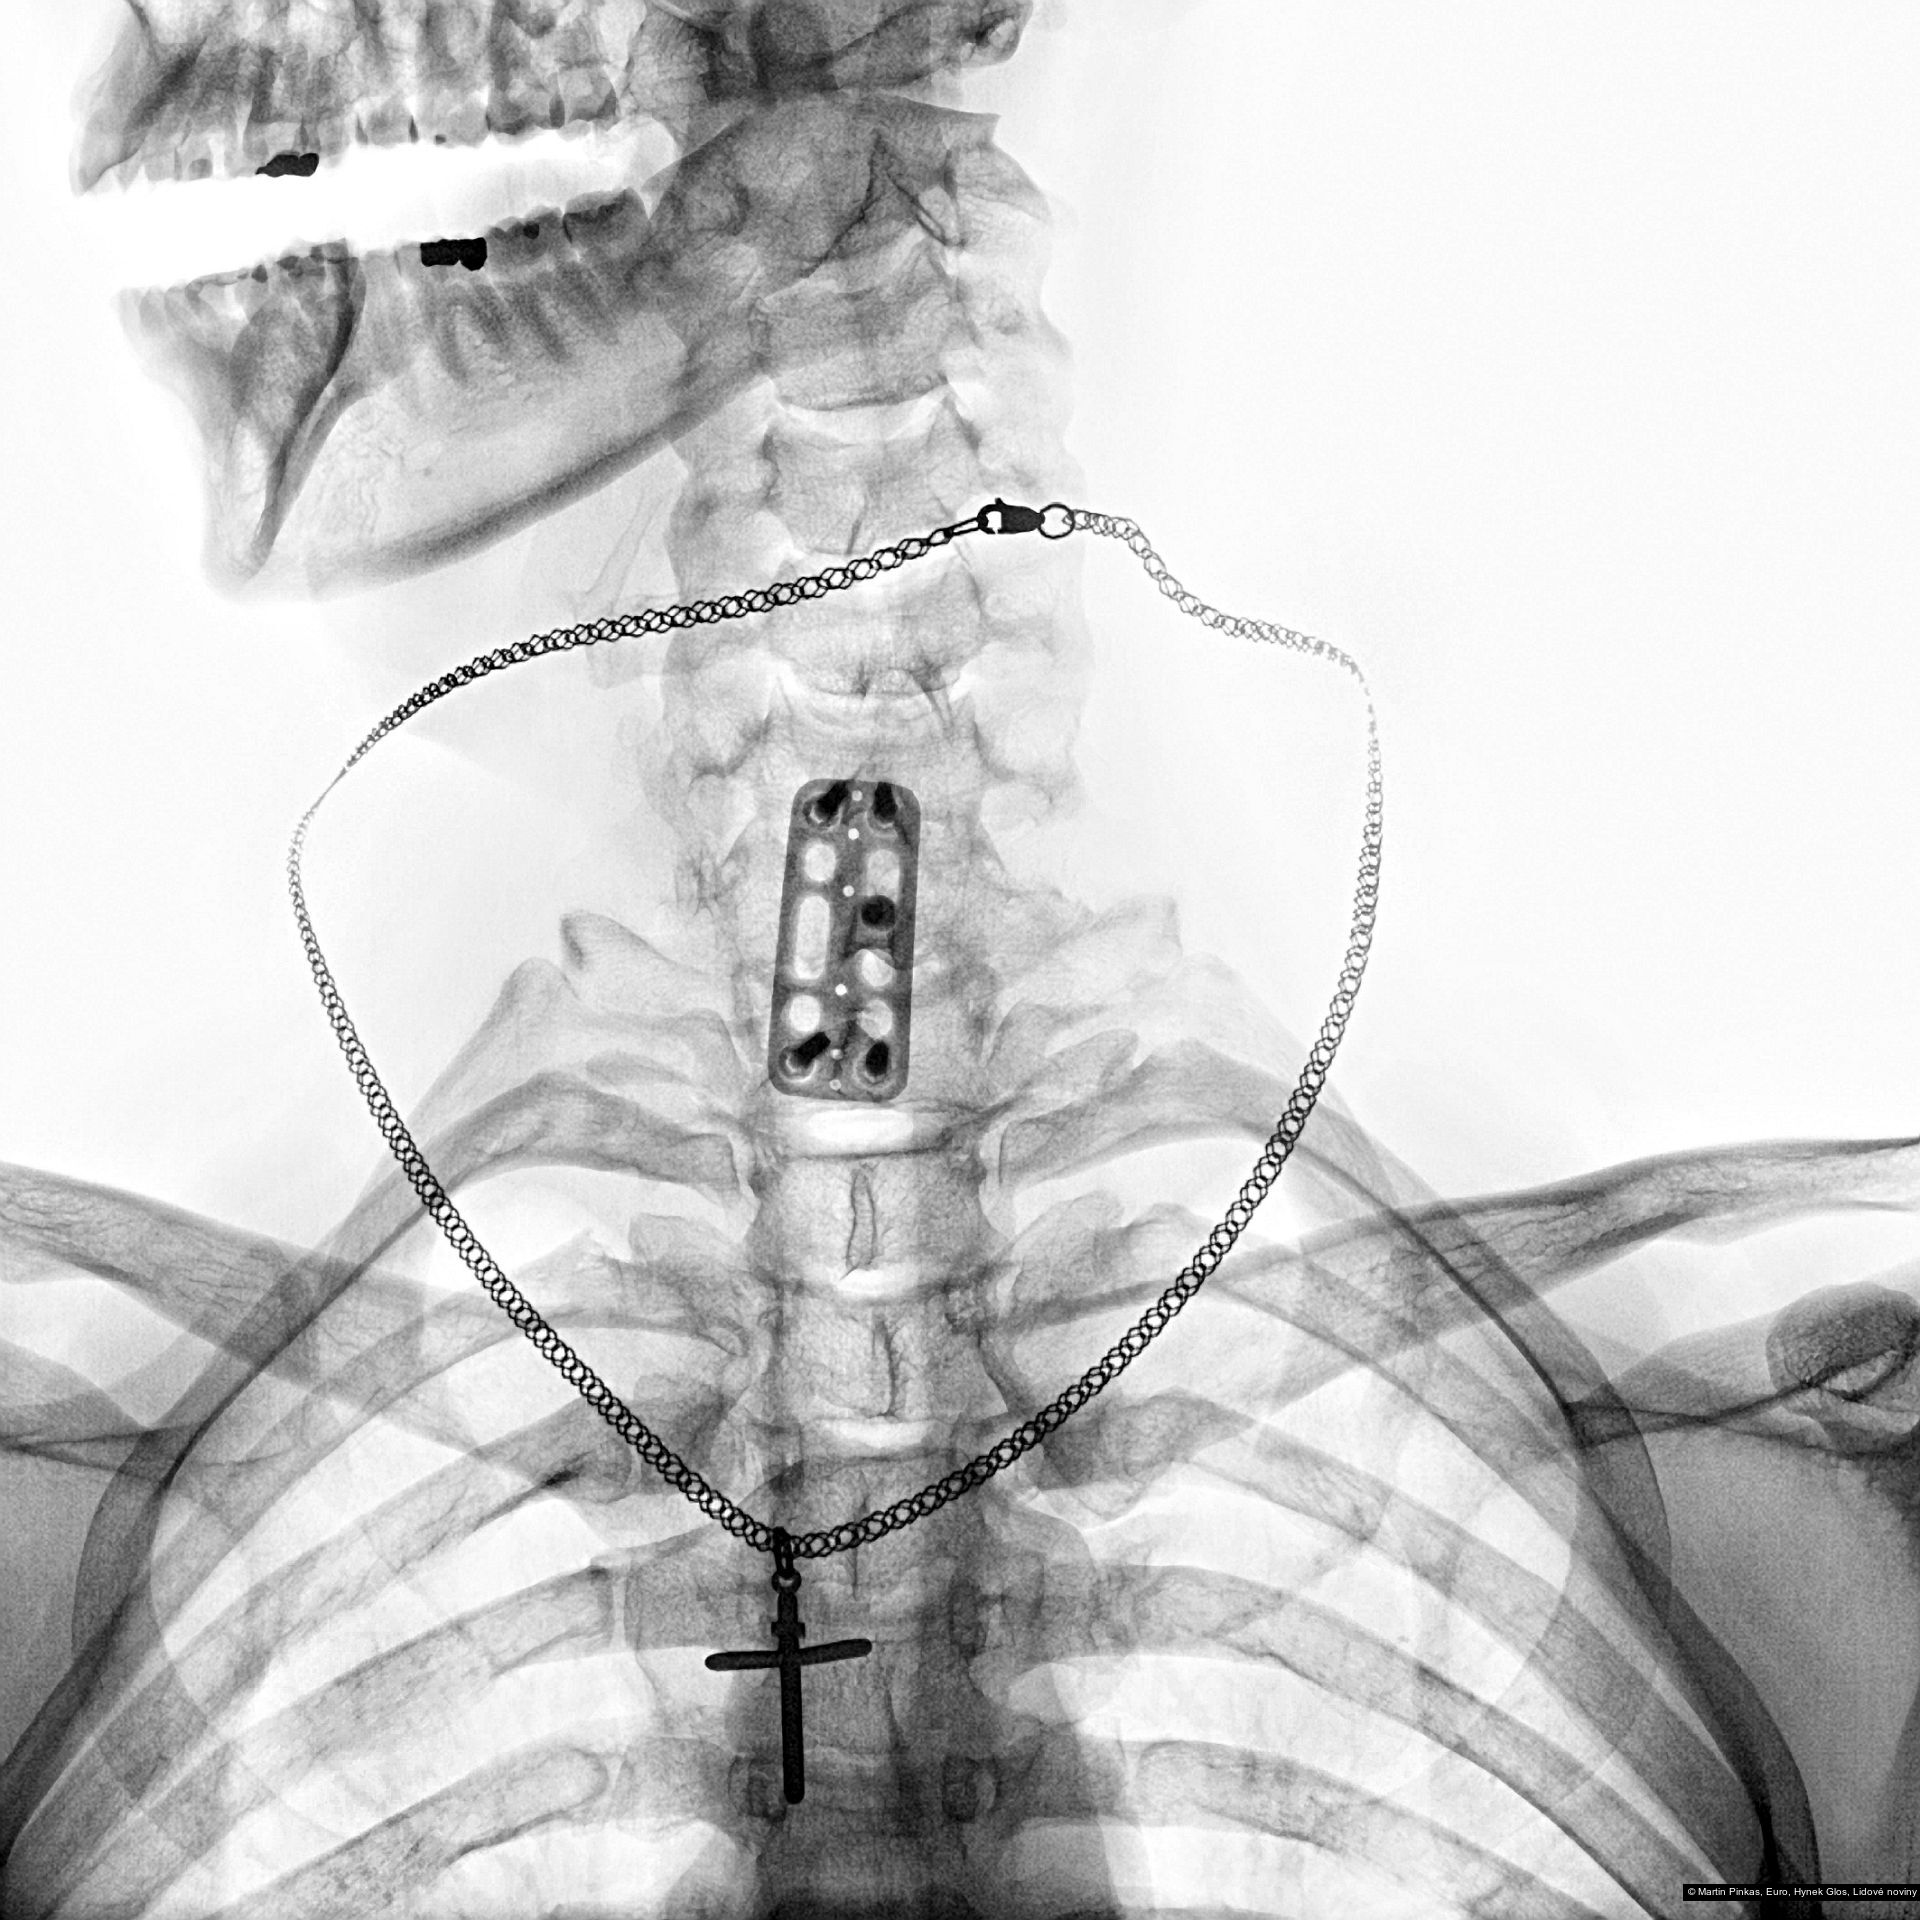

Příspěvek: X-portrait, nelékařské rentgenové portréty handicapovaných sportovců, Praha, Mostiště, 6.8. - 15.9.2010

Autor: Hynek Glos, Martin Pinkas

Příspěvek: X-portrait, nelékařské rentgenové portréty handicapovaných sportovců, Praha, Mostiště, 6.8. - 15.9.2010

Autor: Hynek Glos, Martin Pinkas

Příspěvek: X-portrait, nelékařské rentgenové portréty handicapovaných sportovců, Praha, Mostiště, 6.8. - 15.9.2010

Autor: Hynek Glos, Martin Pinkas

Příspěvek: X-portrait, nelékařské rentgenové portréty handicapovaných sportovců, Praha, Mostiště, 6.8. - 15.9.2010

Autor: Hynek Glos, Martin Pinkas

Příspěvek: X-portrait, nelékařské rentgenové portréty handicapovaných sportovců, Praha, Mostiště, 6.8. - 15.9.2010

Autor: Hynek Glos, Martin Pinkas

Příspěvek: X-portrait, nelékařské rentgenové portréty handicapovaných sportovců, Praha, Mostiště, 6.8. - 15.9.2010

Autor: Hynek Glos, Martin Pinkas

Příspěvek: X-portrait, nelékařské rentgenové portréty handicapovaných sportovců, Praha, Mostiště, 6.8. - 15.9.2010

Autor: Hynek Glos, Martin Pinkas

Příspěvek: X-portrait, nelékařské rentgenové portréty handicapovaných sportovců, Praha, Mostiště, 6.8. - 15.9.2010

Autor: Hynek Glos, Martin Pinkas

Příspěvek: X-portrait, nelékařské rentgenové portréty handicapovaných sportovců, Praha, Mostiště, 6.8. - 15.9.2010

Autor: Hynek Glos, Martin Pinkas